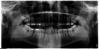

poohpooh Опубликовано 22 сентября, 2009 Поделиться Опубликовано 22 сентября, 2009 Парадонтолог рекомендует удалить все 4-ре восьмерки.Вопрос, надо ли удалять нижние, которые полностью выросли, хотя и стоят кривовато.Говорят, что там карманы, которые чистить трудно, а зубы эти по мнению врачей совсем не нужны.А я думаю, что могут пригодиться потом, если придется ставить мост какой или еще что случится с 7-ми. Да и вообще не хочется удалять без надобности. Болеть пока особо ничего не болит. Недавно почистили камни, теперь, говорят, надо чистить карманы и делать лоскутные операции.Может лучше найти врачей, которые умеют такие карманы чистить? Фото прилагается Ссылка на комментарий

krasik Опубликовано 23 сентября, 2009 Поделиться Опубликовано 23 сентября, 2009 Вопрос, надо ли удалять нижние, которые полностью выросли, хотя и стоят кривовато.Фото прилагаетсяПо снимку, такое ощущение, что весь прикус на восьмерках держится и из-за этого он "Открытый". Или Вы во время снимка нижнюю челюсть сильно вперед выдвинули? Ссылка на комментарий

annda Опубликовано 23 сентября, 2009 Поделиться Опубликовано 23 сентября, 2009 Показанием для удаление в вашем случае является несколько факторов. Во-первых - их бесполезность с жевательной точки зрения. Затем - выдвижение вверх в связи с неправильным положением антагонистов (верхних восьмерок). Плохая гигиена коронок с "дальней" стороны и потеря костной поддержки между 7 и 8 зубами в связи с хроническим воспалением. Это если вкратце. Естественно, Вы можете чистить карманы и стойко переносить неоднократный физический и, не побоюсь этого слова, материальный дискомфорт, поскольку зубы Ваши и последнее слово остается за Вами. Однако зачем платить за то, что "не работает и работать не планирует"?! Как вариант - сохранить, чтобы потом пересадить на место"потерянных" из-за воспаления 7-х или других жевательных зубов... Ещё надо добавить,что соседние 7ки помрут именно из-за них.И удивительно ,как это ещё не случилось,хотя слева на дистальной стенке 7ки уже виднеется нечто подозрительное.После удаления никто никуда не поедет.И ничто...Пациенту-не хотите,не удаляйте,никто насильно этого сделать не сможет.Черпайте все эти прелести полной ложкой.Останетесь внизу со съёмниками в молодом возрасте-тоже ваше право. Ссылка на комментарий

poohpooh Опубликовано 23 сентября, 2009 Автор Поделиться Опубликовано 23 сентября, 2009 to krasik:Да нижняя челюсть на снимке вперед выдвинута. Так велели, когда снимок делали. to annda:возраст уже как бы не совсем молодой. так лет 40 где-то. Ссылка на комментарий

витязь Опубликовано 26 сентября, 2009 Поделиться Опубликовано 26 сентября, 2009 Парадонтолог рекомендует удалить все 4-ре восьмерки....однозначно удалять!и парадонтолог прав на все 100%.а)в области нижних восьмерок наличие карманов,что не является благотворной ситуацией для соседних 7 б)на верхней челюсти ситуация еще веселее-они пытаются вывернуть 7-ки,за счет своего наклона Ссылка на комментарий